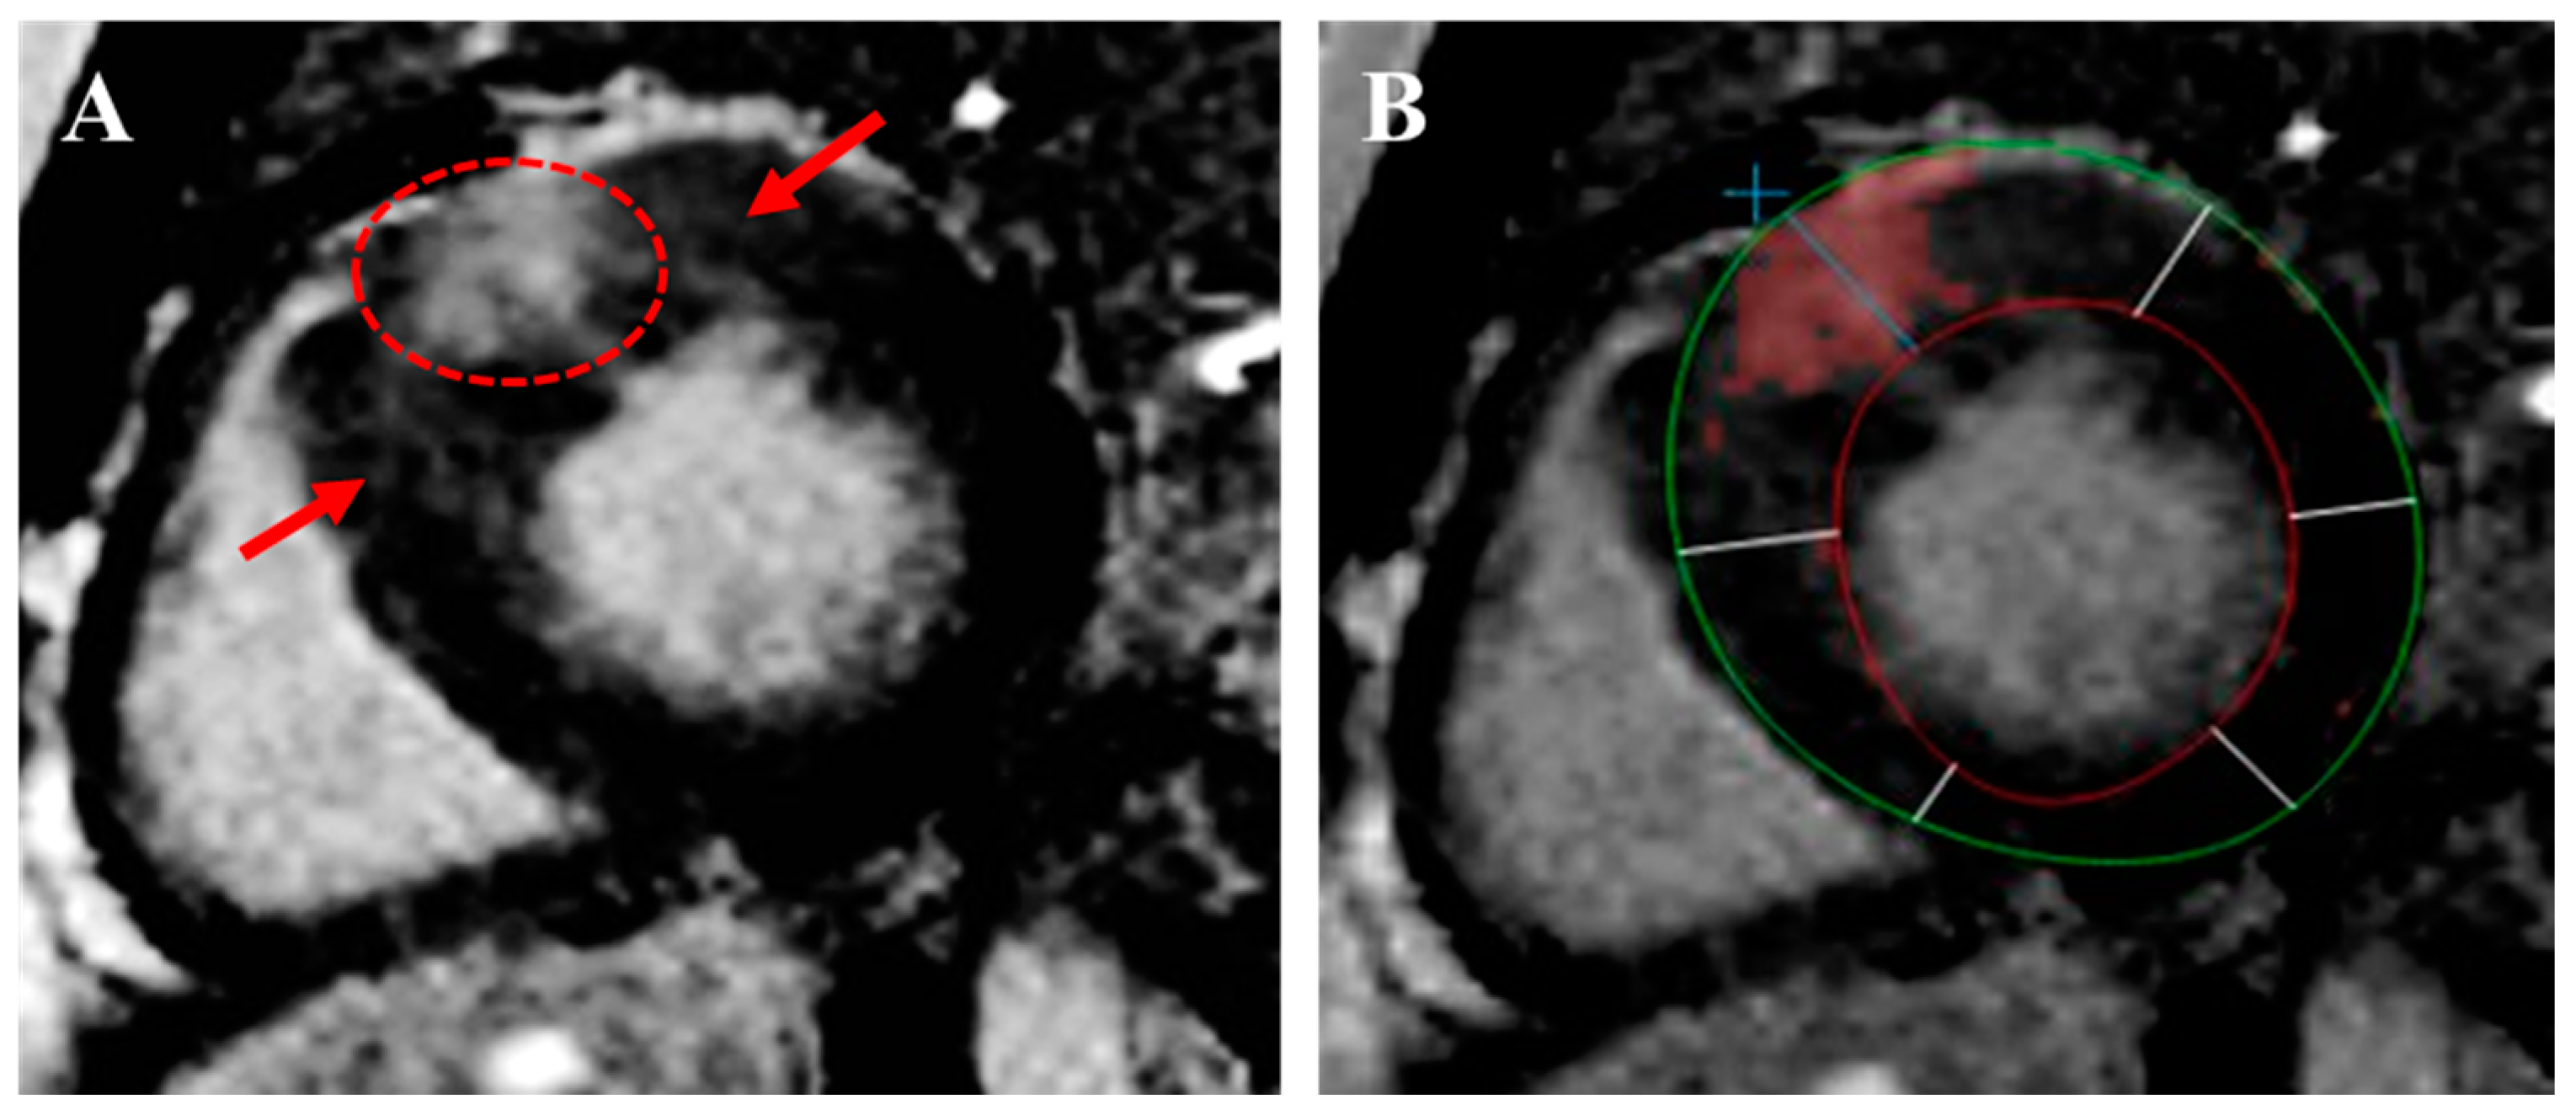

2.8. Myocardial Fibrosis

3.3. Cardiac Magnetic Resonance Imaging

- Kiaos, A.; Daskalopoulos, G.N.; Kamperidis, V.; Ziakas, A.; Efthimiadis, G.; Karamitsos, T.D. Quantitative Late Gadolinium Enhancement Cardiac Magnetic Resonance and Sudden Death in Hypertrophic Cardiomyopathy: A Meta-Analysis. JACC Cardiovasc. Imaging 2024, 17, 489–497. [Google Scholar] [CrossRef]

- Mentias, A.; Raeisi-Giglou, P.; Smedira, N.G.; Feng, K.; Sato, K.; Wazni, O.; Kanj, M.; Flamm, S.D.; Thamilarasan, M.; Popovic, Z.B.; et al. Late Gadolinium Enhancement in Patients with Hypertrophic Cardiomyopathy and Preserved Systolic Function. J. Am. Coll. Cardiol. 2018, 72, 857–870. [Google Scholar] [CrossRef]

- Chan, R.H.; Maron, B.J.; Olivotto, I.; Pencina, M.J.; Assenza, G.E.; Haas, T.; Lesser, J.R.; Gruner, C.; Crean, A.M.; Rakowski, H.; et al. Prognostic value of quantitative contrast-enhanced cardiovascular magnetic resonance for the evaluation of sudden death risk in patients with hypertrophic cardiomyopathy. Circulation 2014, 130, 484–495. [Google Scholar] [CrossRef] [PubMed]